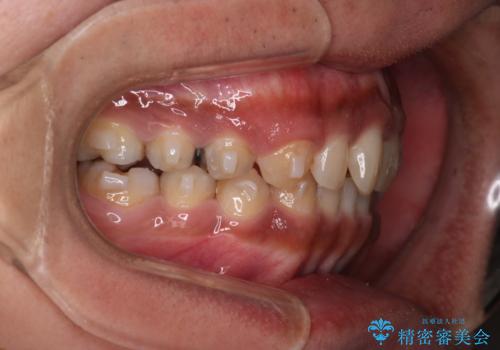

【モニター】インビザライン 前歯の捻れを治したい

- 30代男性

- 矯正装置

- インビザライン

- 治療期間

- 1年6ヶ月

- 上下の前歯のがたつきを主訴に来院されました。インビザラインで治療可能と判断致しましたので、IPR(歯と歯の間を削る処置)と歯列弓拡大をして

がたつきをとる治療計画を立てました。

マウスピースをしっかり使用していただいたことで、主訴である前歯のがたつきも改善され

リファイメントも1回のみで治療を終了することが出来ました。